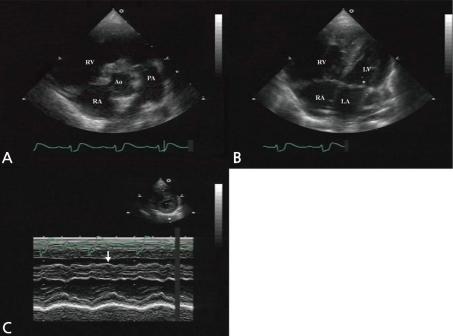

Partial anomalous pulmonary vein connection (PAPVC) is a rare congenital abnormal cardiac defect involving the pulmonary veins draining into the right atrium (RA) directly or indirectly by venous connection. Ninety percent of PAPVCs are accompanied by atrial septal defect (ASD). To our knowledge, there is no previous report of PAPVC with ventricular septal defect (VSD) without ASD in Korea, and in this paper, we report the first such case. A 2-day-old girl was admitted into the Chonnam National University Hospital for evaluation of a cardiac murmur. An echocardiogram revealed perimembranous VSD without ASD. She underwent patch closure of the VSD at 5 months of age. Although the VSD was completely closed, she had persistent cardiomegaly with right ventricular volume overload, as revealed by echocardiography. Three years later, cardiac catheterization and chest computed tomography revealed a PAPVC, with the right upper pulmonary vein draining into the right SVC. Therefore, correction of the PAPVC was surgically performed at 3 years of age. We conclude that it is important to suspect PAPVC in patients with right ventricular volume overload, but without ASD.

部分性肺静脉异位连接(PAPVC)是一种罕见的先天性心脏缺陷,涉及肺静脉通过静脉连接直接或间接引流至右心房(RA)。90%的PAPVC伴有房间隔缺损(ASD)。据我们所知,韩国此前尚无无ASD的PAPVC合并室间隔缺损(VSD)的报道,本文报告首例此类病例。一名2日龄女童因心脏杂音入院全南国立大学医院评估。超声心动图显示为膜周部VSD,无ASD。她在5个月大时接受了VSD修补术。尽管VSD完全闭合,但超声心动图显示她仍有持续的心脏扩大及右心室容量超负荷。3年后,心导管检查和胸部计算机断层扫描显示存在PAPVC,右上肺静脉引流至右头臂静脉。因此,在3岁时对PAPVC进行了手术矫正。我们得出结论,对于右心室容量超负荷但无ASD的患者,怀疑PAPVC很重要。